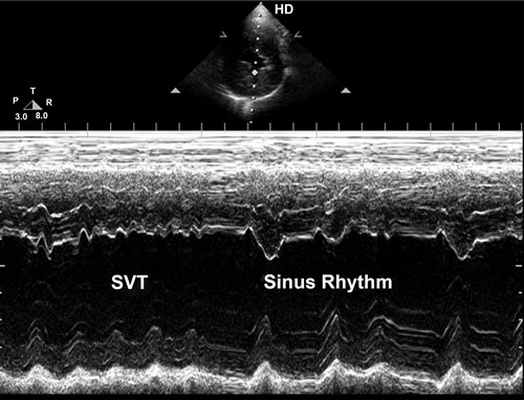

Эхокардиографическое исследование, показывающее увеличенный диаметр желудочка в конце диастолы, приведено на рис. 2. Надавливание на глазные яблоки животного снова временно прервало наджелудочковую тахикардию, что позволило вычислить фракционное укорочение во время аритмии (23%) и во время синусового ритма (28%), подчёркивая таким образом его влияние на сократительную способность. Клапаны сердца были без изменений и полностью выполняли свои функции.

| |

| Рис. 2. Поперечное изображение левого желудочка в м-режиме, показывающее увеличение диаметра левого желудочка в конце диастолы, а также два различных сценария сократимости. Во время наджелудочковой тахикардии (НЖТ) присутствует явное нарушение сократимости, что демонстрируется минимальным изменением желудочковой камеры в процессе сердечного цикла. При временном восстановлении синусового ритма систолические смещения межжелудочковой перегородки и свободной стенки левого желудочка вызывают явное уменьшение просвета желудочка, таким образом увеличивая ударный объём. Вычисленное фракционное укорочение было равно 23% в время НЖТ и 28% во время синусового ритма |